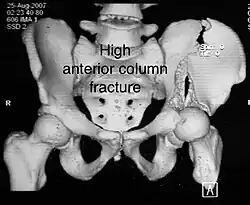

| Anterior column | This fracture is uncommon, typically occurring when the injuring force is applied from the side, against the greater trochanter of the femur bone, as in a fall on the side or being hit on the side. Depending on the location, the fractures are described as very low, low, intermediate and high anterior column fracture. | Anterior column + posterior hemi transverse | In this variety of fractures, the posterior or ilio ischial column is broken as a transverse fracture, while the anterior or ilio pubic column is broken into multiple pieces. Part of the weight-bearing dome in this variety of fractures is still attached to that part of the iliac wing, which forms part of the iliac joint. This type of injury has to be differentiated from both column fractures, where the weight-bearing dome is a floating piece not attached directly to the bone-forming sacroiliac joint.

- Anterior column fracture: Obturator oblique view

High anterior column fracture 3 D CT scan picture

High anterior column fracture 3 D CT scan picture -